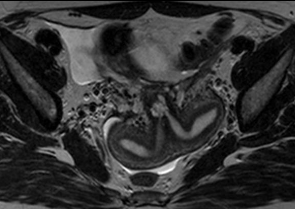

32세 여성이 난임으로 내원하였다. 과거에 세 번의 자연유산이 있었다. 남편의 정액 검사 결과는 정상이었다. 골반 MRI 및 자궁나팔관조영 검사 결과이다. 치료는?

• MRI상 자궁은 부피가 크고 앞쪽으로 기울어져 있으며, 두 개의 자궁강이 septum(low signal density로 보이고 있음)로 나뉘어 있다. 이 저신호는 자궁경부까지 뻗어 있으며, fundus의 평평한 윤곽이 관찰된다. 이는 완전 중격자궁(complete septate uterus)을 시사한다. 쌍각자궁의 경우 fundus에서 1cm 이상으로 깊게 함입되어 있다.